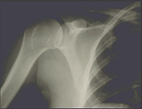

Here is an x-ray of someone's shoulder, maybe mine.

Mine was broken and will heal over time.